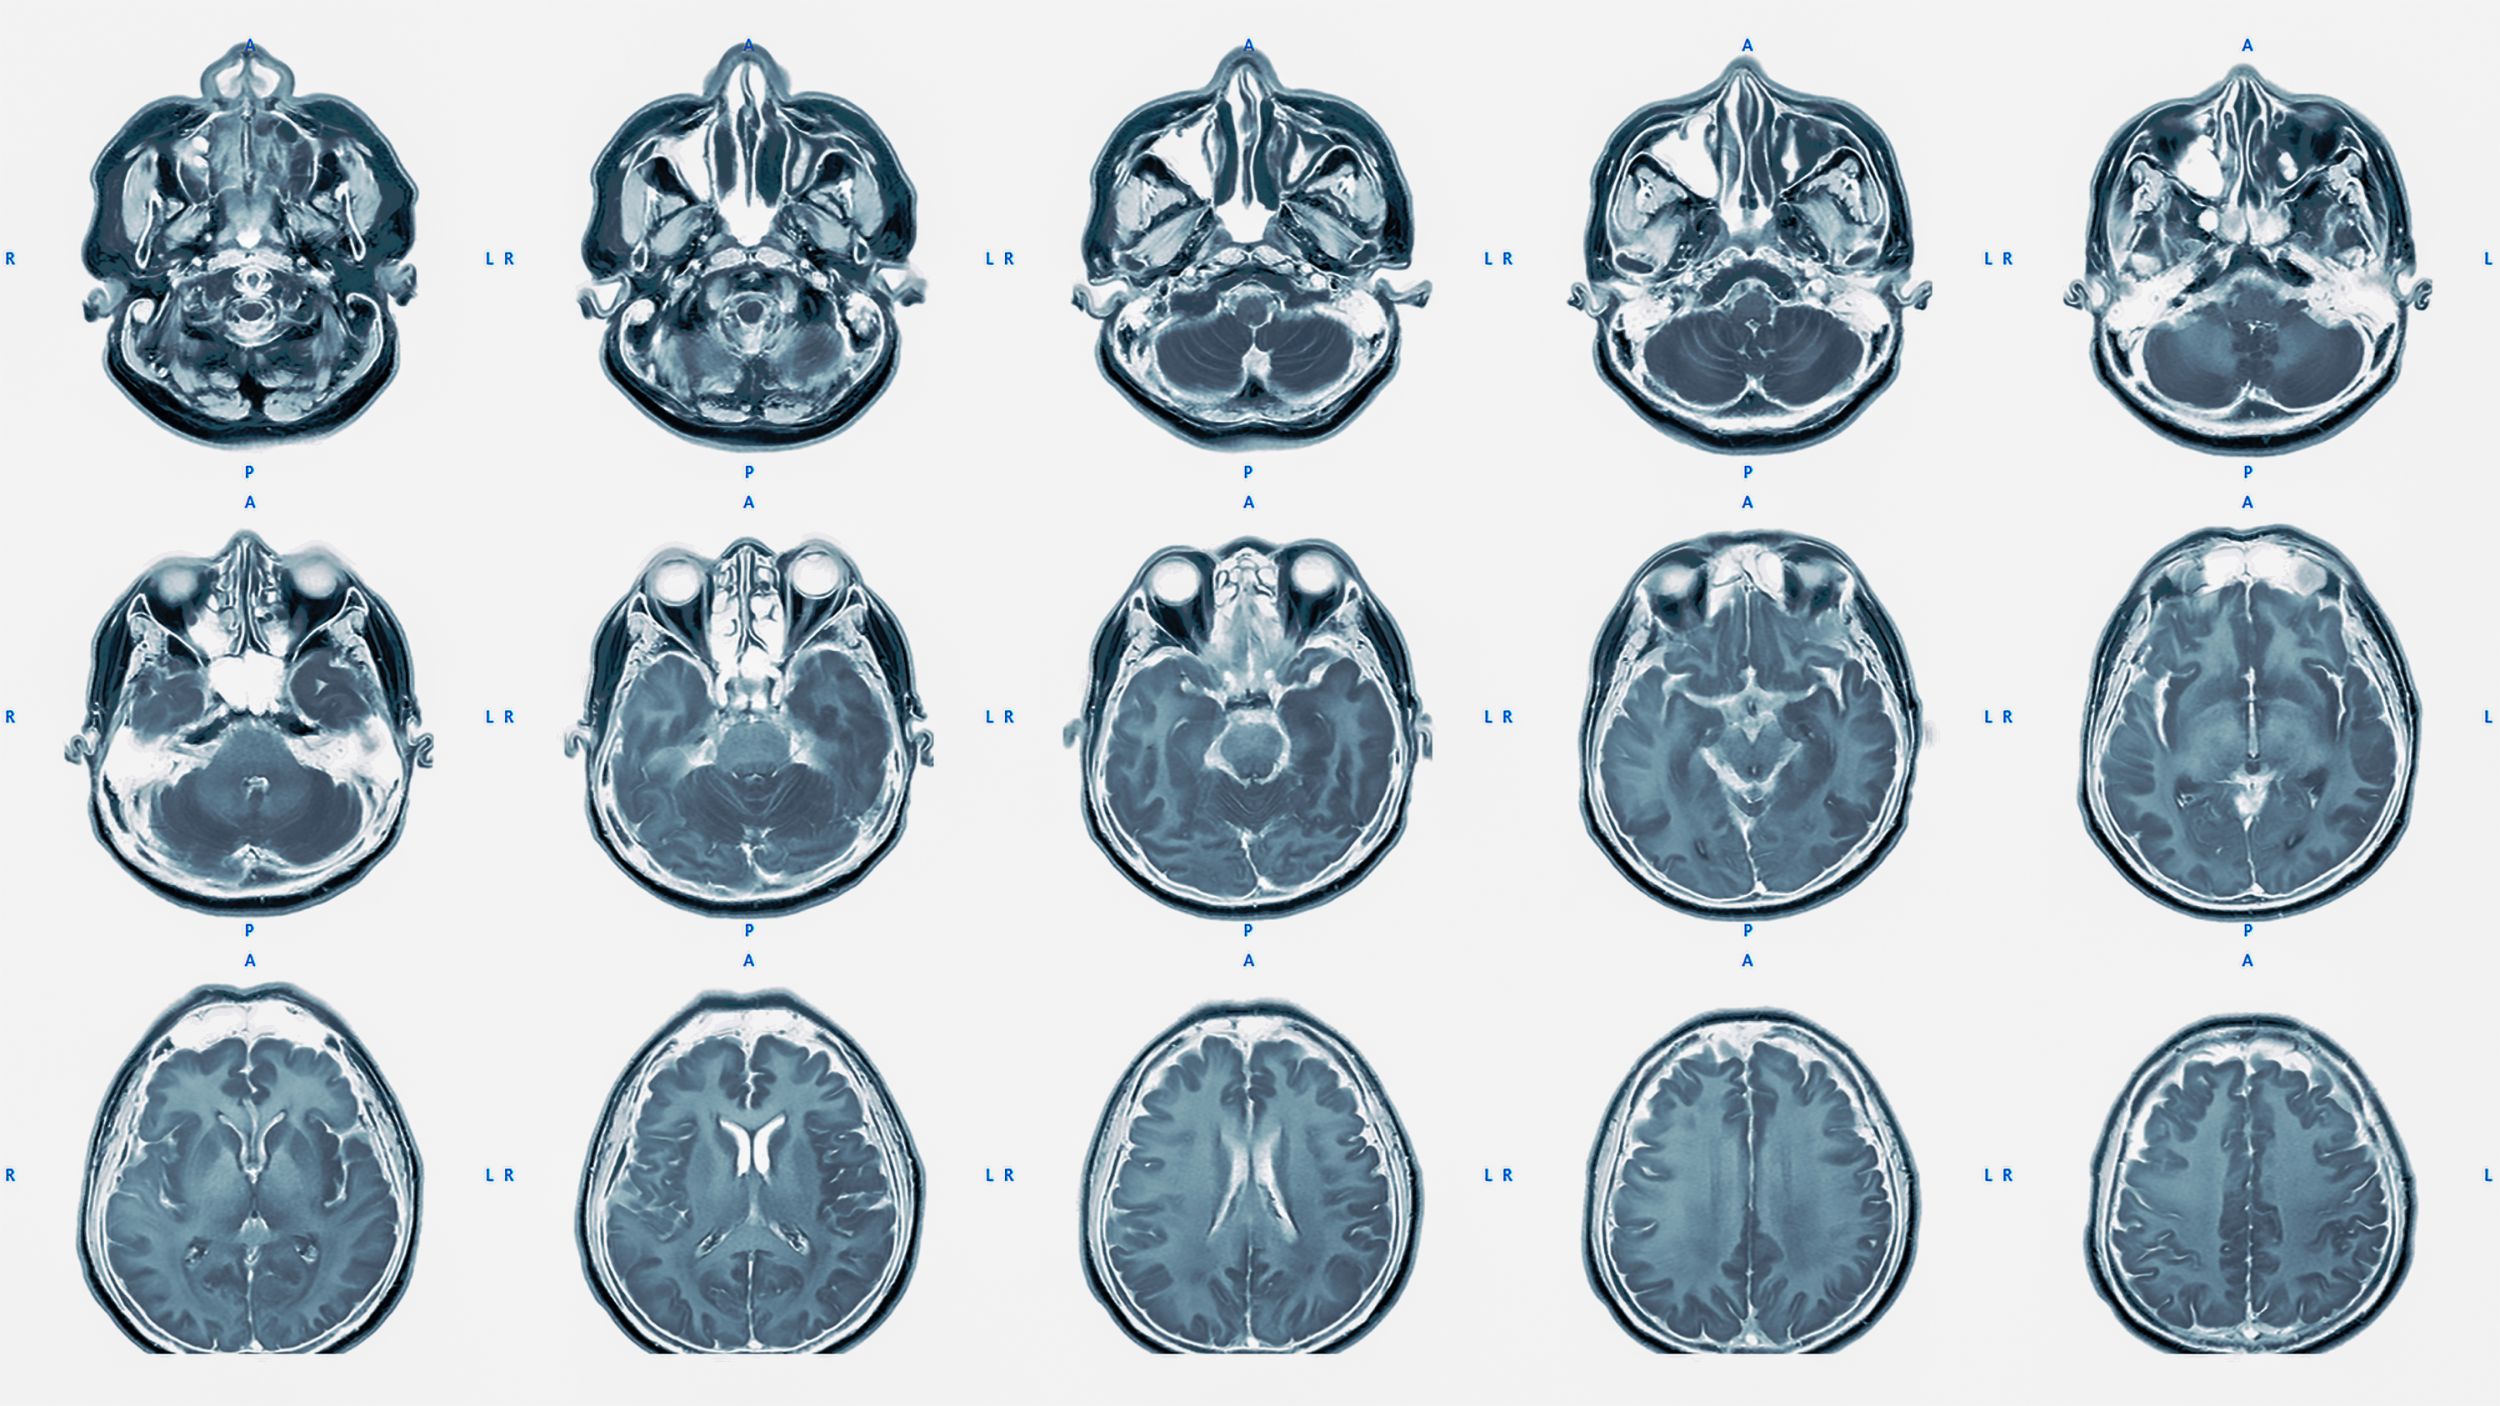

tumeurs rares IRM

L'OMS décrit plus de 120 types de tumeurs différentes du système nerveux central. Outre les métastases cérébrales, les méningiomes et les gliomes, plus fréquents, il existe également des tumeurs plus rares comme les adénomes hypophysaires, les schwannomes vestibulaires ou les lymphomes du système nerveux central.